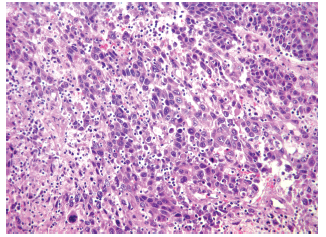

The study group included 14 patients with HCC and liver cirrhosis (45.2%) (Figure 1) and 17 patients with HCC without liver cirrhosis (54.8%) (Figure 2). The control group (patients with chronic liver disease) included 12 patients with liver fibrosis (44.5%), 7 patients with primary biliary cirrhosis (25.9%), 3 patients with autoimmune hepatitis (11.1%), and 5 patients with cirrhosis due to other causes (18.5%).

Morphologic data were characterized for signs of HCC. Trabecular-type HCC was predominant, shown in 26 patients (83.9%),versus solid tumor type, shown in 5 patients (16.1%). Degree of malignancy according to the Edmondson-Steiner system showed 8 patients (25.8%) having grade I, 10 patients (32.3%) having grade II, 9 patients (29.0%) having grade III, and 4 patients (12.9%) having grade IV (Figures 3-6 show resection of archived materials).

Figure 2. Hepatocellular Carcinoma

Figure 4. Hepatocellular Carcinoma Showing Trabecular Structure With Areas of Proliferation and Coarse Connective Tissue Fibers (hematoxylin and eosin staining; ×200)